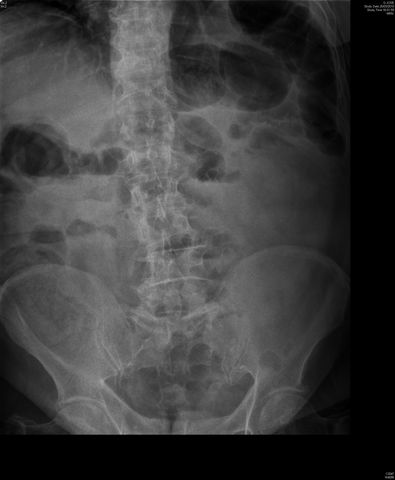

Dilatación colónica. Diverticulosis.